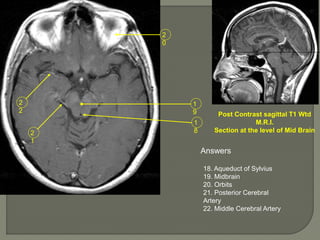

Post Contrast sagittal T1 Wtd

M.R.I.

Section at the level of Mid Brain

Answers

18. Aqueduct of Sylvius

19. Midbrain

20. Orbits

21. Posterior Cerebral

Artery

22. Middle Cerebral Artery